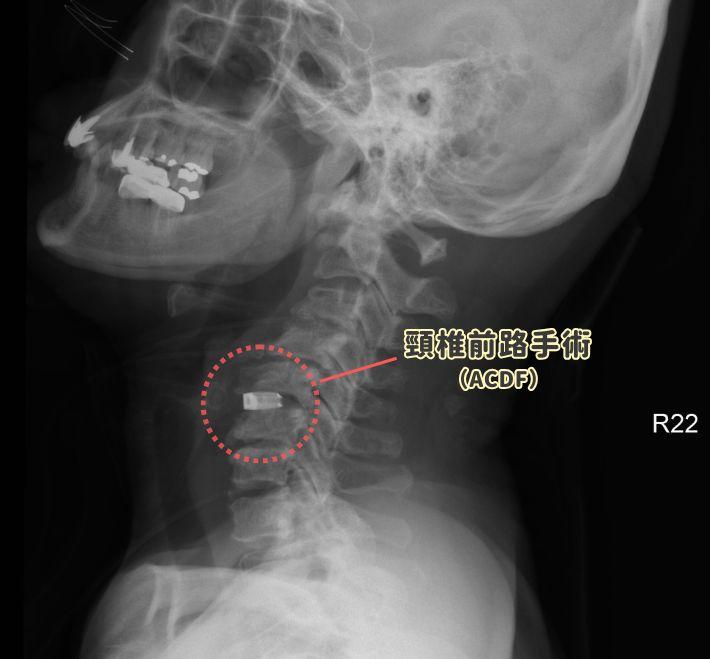

頸椎椎間盤突出一定要開大刀嗎?醫師解析三種主流微創手術與恢復期

手指發麻、走路不穩?頸椎椎間盤突出不一定要傳統大手術。本文由張建鈞醫師解析 ACDF 前路融合、ADR 人工椎間盤與後路內視鏡三種微創術式。整理最新PubMed文獻數據,揭露真實併發症機率(低於 10%)與術後恢復期對比。幫助您在保留頸部靈活度與緩解神經壓迫間做出決策。